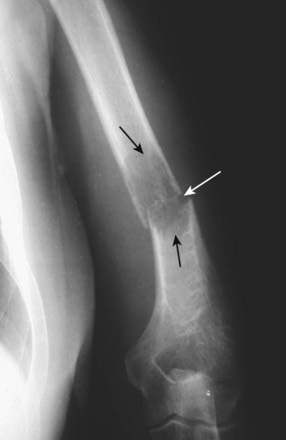

Figure 21-9 Avascular necrosis of the left femoral head in a patient on long-term steroids for lupus erythematosus.

A close-up view of the left femoral head shows a zone of increased sclerosis in the superior aspect of the femoral head (solid white arrows), a characteristic finding of avascular necrosis of the head. The linear, subcortical lucency (solid black arrow) represents subchondral fractures seen with this disease, called the crescent sign. Notice that the disease is isolated to the femoral head and involves neither the joint space nor the acetabulum, i.e., this it is not an arthritis.